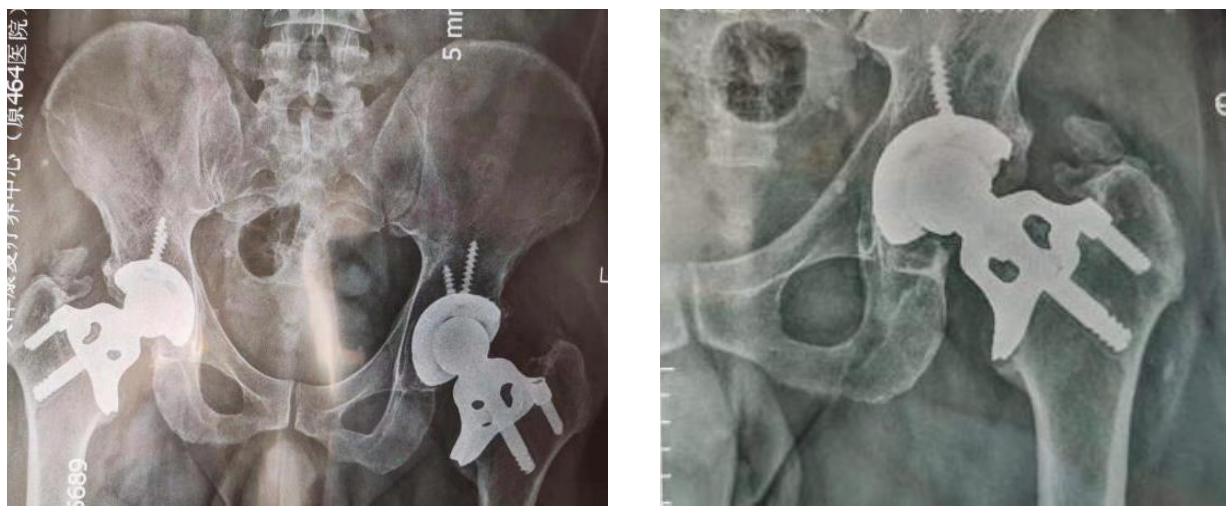

無股骨柄式人工髖關節

無柄式人工髖關節是一種較新的人工髖關節設計,相較於傳統的全置換式人工關節,它保留了大部分的原始髖關節結構,只移除表面壞死組織,減少對骨骼的破壞並避免掏空骨髓腔,因此可改善術後應力遮蔽現象,並有利於未來進行二次手術。

全人工髖關節幾何形狀及固定方式對於股骨近 端應力遮蔽之影響研究

The Effect of Geometry and Fixation Modes of Total Hip Prosthesis on the Stress Shielding of Proximal Femur in Total Hip Arthroplasty